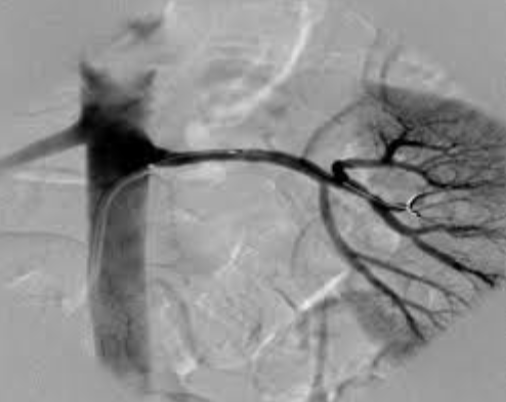

Il est principalement utilisé pour dépister ou surveiller les maladies artérielles, comme l’athérosclérose, les sténoses (rétrécissements artériels), les occlusions ou les anévrismes. Il arrive souvent en complément d’une exploration cardiaque.

On le réalise fréquemment au niveau des artères des membres inférieurs en cas de douleurs à la marche (artériopathie oblitérante), des carotides pour évaluer le risque d’accident vasculaire cérébral, ou encore des artères rénales et abdominales selon les indications.

Le Doppler artériel fournit des informations essentielles : qualité du flux sanguin, présence de plaques d’athérome, degré de rétrécissement et retentissement sur la circulation.

Ces données permettent un diagnostic précoce et orientent les décisions thérapeutiques, qu’il s’agisse de mesures médicales, de modifications du mode de vie ou d’une intervention vasculaire (parfois même en urgence).